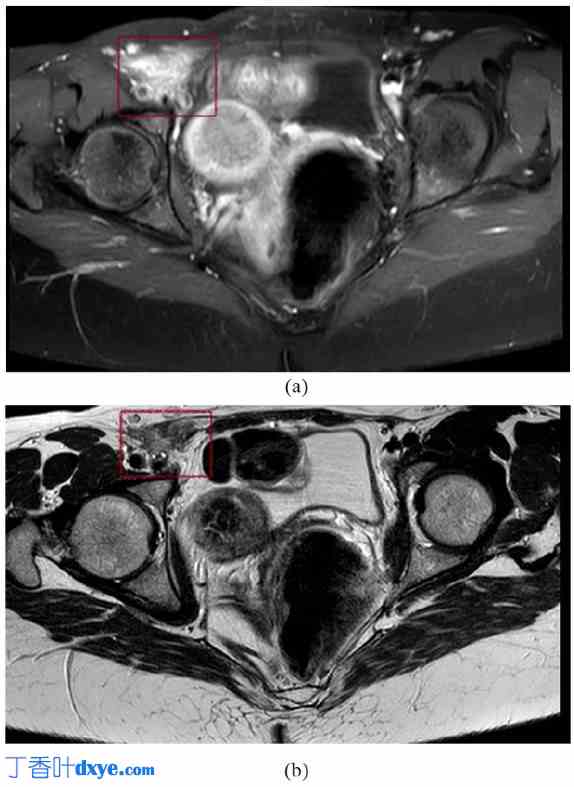

一年后,患者因右腹股沟区疼痛加剧且持续一整天而再次来院就诊。她再次接受了腹部和直肠超声检查。超声检查结果提示:(1) 子宫肌瘤最大直径为50 mm,粘连于右侧卵巢和子宫。(2) 一个11 mm × 20 mm的子宫内膜异位结节粘连于宫颈后段直肠下段前浆膜。MRI 检查显示一个19 mm × 50 mm的低回声肿块。该肿块在T1加权像(图1(a))和T2加权像(图1(b))中的信号均低于肌肉。根据病史,诊断为圆韧带子宫内膜异位症。多普勒超声检查显示肿块内血流水平较低。肿块靠近下腹壁动脉起点。盆腔动脉(尤其是髂总动脉和髂外血管)的计算机断层扫描(CT)血管造影检查结果正常。该患者适合接受腹腔镜手术。

图 1.

1.jpg

(a) 磁共振成像 T1 加权像,显示一个 19 × 50 mm 的低回声实性肿块,其信号低于肌肉;(b) 同一病变的 T2 加权像。